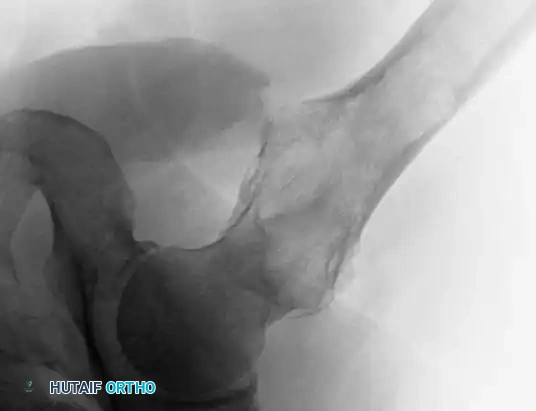

Image

CT scans demonstrating the extensive cortical destruction of the lesions, highlighting the imminent biomechanical failure and the absolute need for prophylactic fixation.

For extensive lytic lesions of the proximal femur (as seen in the provided CT scans), prophylactic stabilization is indicated to prevent catastrophic fracture.